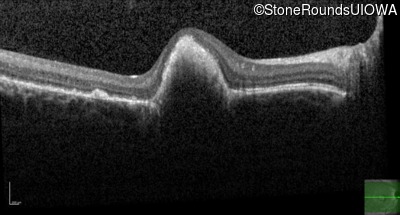

Best Disease (IIB)

Age at visit: 14 years

This 15 year old girl came to medical attention during a routine athletic vision screening when the acuity in her right eye was observed to be abnormal.

Diagnosis & molecular findings

Disease Gene Allele 1 variant(s) Allele 2 variant(s) Inheritance mode

Best Disease BEST1 Asp228Glu GAC>GAG Asn259 ins2aacAA AR